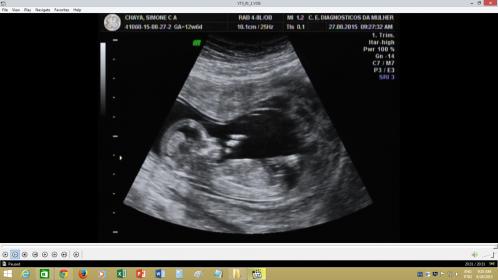

Hello ladies, would really appreciate if you could help us figure out what this little cutie here is? Thank you very much.![]()

My sister's baby, any thoughts girls?

I think boy too

I'm leaning toward boy too!

boy

Boy :-)

Boy from me!